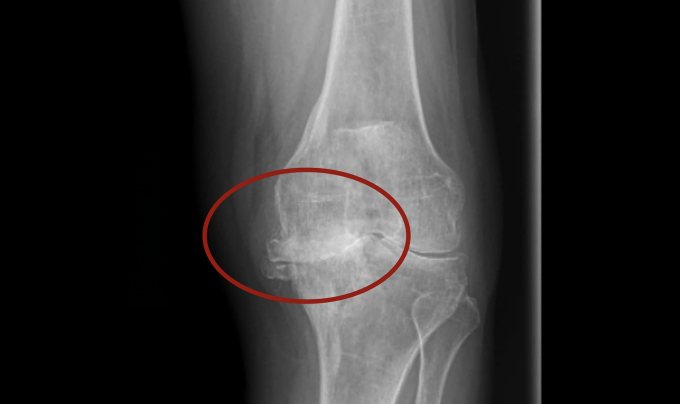

Sẩn cục khắp tay chân do viêm da mạn tính

TP HCM- Ông Hậu, 55 tuổi, nổi sẩn cục khắp tay, chân suốt hai năm, ngứa nhiều, cào gãi gây xước da, bác sĩ chẩn đoán viêm da mạn tính.